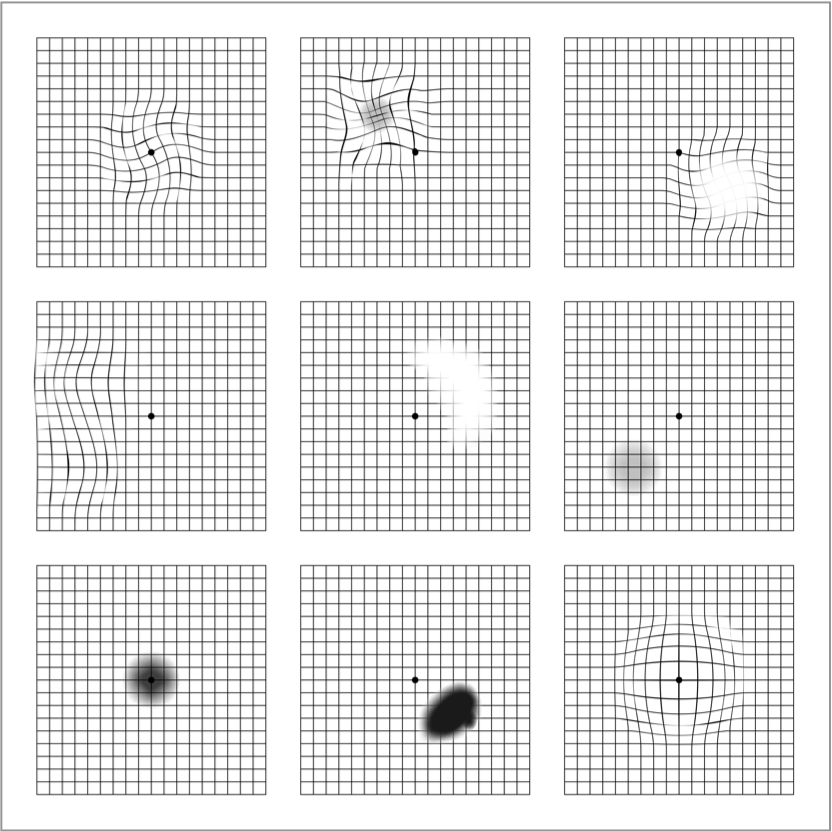

La rejilla de Amsler es una herramienta de autocomprobación esencial1 y fácil de usar que sirve para detectar cambios tempranos en su visión. Estos cambios pueden incluir distorsión (líneas rectas que aparecen onduladas), manchas borrosas u oscuras.

Es importante no confiar en la rejilla de Amsler para el diagnóstico, ya que no puede sustituir a los exámenes oculares regulares. La única forma de diagnosticar la DMAE es someterse a un examen ocular, que incluya una revisión de la mácula, por parte de un optometrista u oftalmólogo. Tenga en cuenta que los cambios en la visión en una cuadrícula de Amsler también pueden ser un signo de otra enfermedad ocular distinta a la DMAE.